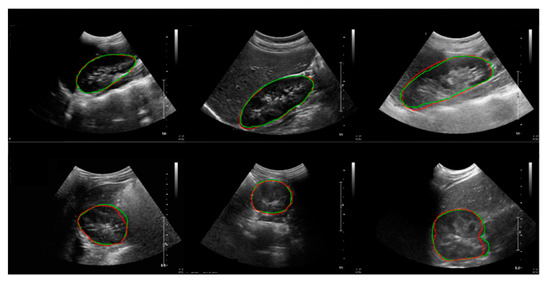

2.3.2. US Images and Image Processing Program

2.4. Automation of Volume Measurement by Hybrid Learning

2.4.1. Datasets